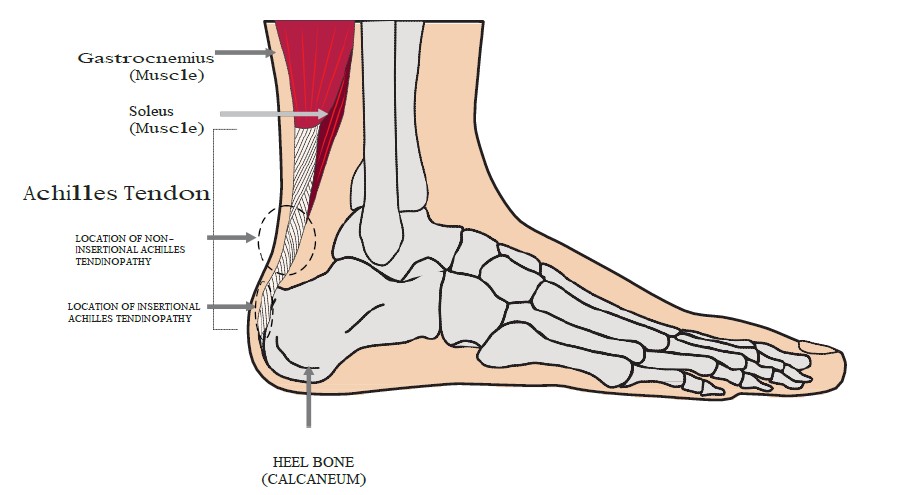

Product Item: Swollen achilles tendon treatment dealsAchilles tendon injuries healthdirect deals, Achilles Tendinitis Symptoms Treatment deals, How to Relieve Achilles Tendonitis in SECONDS deals, Achilles Tendinitis OrthoInfo AAOS deals, Achilles Tendinitis Exercises to Heal and Strengthen Your Tendon deals, Achilles Tendon Pain Causes Treatments Prevention deals, Achilles tendon Overview Mayo Clinic Orthopedics Sports Medicine deals, Achilles Tendonitis Symptoms and Treatment Caruso Foot and Ankle deals, Tendinopathy Symptoms Causes Treatment deals, Achilles Tendinitis OrthoInfo AAOS deals, Chronic Achilles Tendon Pain Diagnosis Treatment HSS deals, Know the Symptoms of Achilles Tendonitis Tendinopathy Gait Happens deals, Achilles tendinopathy Symptoms causes and treatment Bupa UK deals, Achilles Tendon Injuries deals, Swollen Achilles tendon Why does it swell and when can I exercise deals, Heal Your Achilles Tendonitis At Home Achilles Tendon Treatment deals, Achilles Tendonitis FootEducation deals, Achilles Tendinopathy Symptoms Treatments Recovery deals, Achilles Tendinopathy Causes Symptoms Treatment The Feet People Podiatry deals, How to fix Insertional Achilles Tendonitis deals, Achilles tendinitis Symptoms causes Mayo Clinic deals, Back of Achilles Tendon Heel Pain Shoes Orthotics Home Treatment deals, Achilles Tendonitis Causes Symptoms Signs Gleneagles Hospital deals, Achilles Tendinopathy NHS Lanarkshire deals, Achilles Tendinitis in Children Causes and Treatment deals, Achilles Tendonitis Common Symptoms Diagnosis and Treatment deals, Achilles Tendinitis Types Symptoms Causes Diagnosis Treatment and More deals, Achilles Tendinitis River Forest Rheumatoid Arthritis Elmhurst deals, Achilles tendinopathy is when you have micro tears in the tendon deals, Achilles swelling sales pain deals, Achilles Tendon Burning Pain Treatment Achilles Tendonitis deals, Achilles Tendinopathy Causes Symptoms Treatment The Feet People Podiatry deals, Exercises for Achilles pain Three gentle moves to get your rehab going deals, Achilles Tendinosis Treatment Symptoms and More deals, Achilles deals tendon swelling deals.